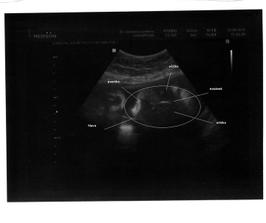

15.7. Jsem byli v Podolí na velkém utz ve 20tt, jsme zdraví a máme všechno, co máme mít. A jsme KLUK 🙂

22.9. Kontrola dopadla skvěle, vypadáme teda asi o 6 dní starší, ale jsme naprosto v pořádku a váhový odhad je 1798g. Jsme prý na 100% kluk. Jinak jsme pořád ještě asi 3kg pod původní váhou. Ale podle domácí váhy asi 5kg. Tak jen ať nám to ještě chvíli vydrží.